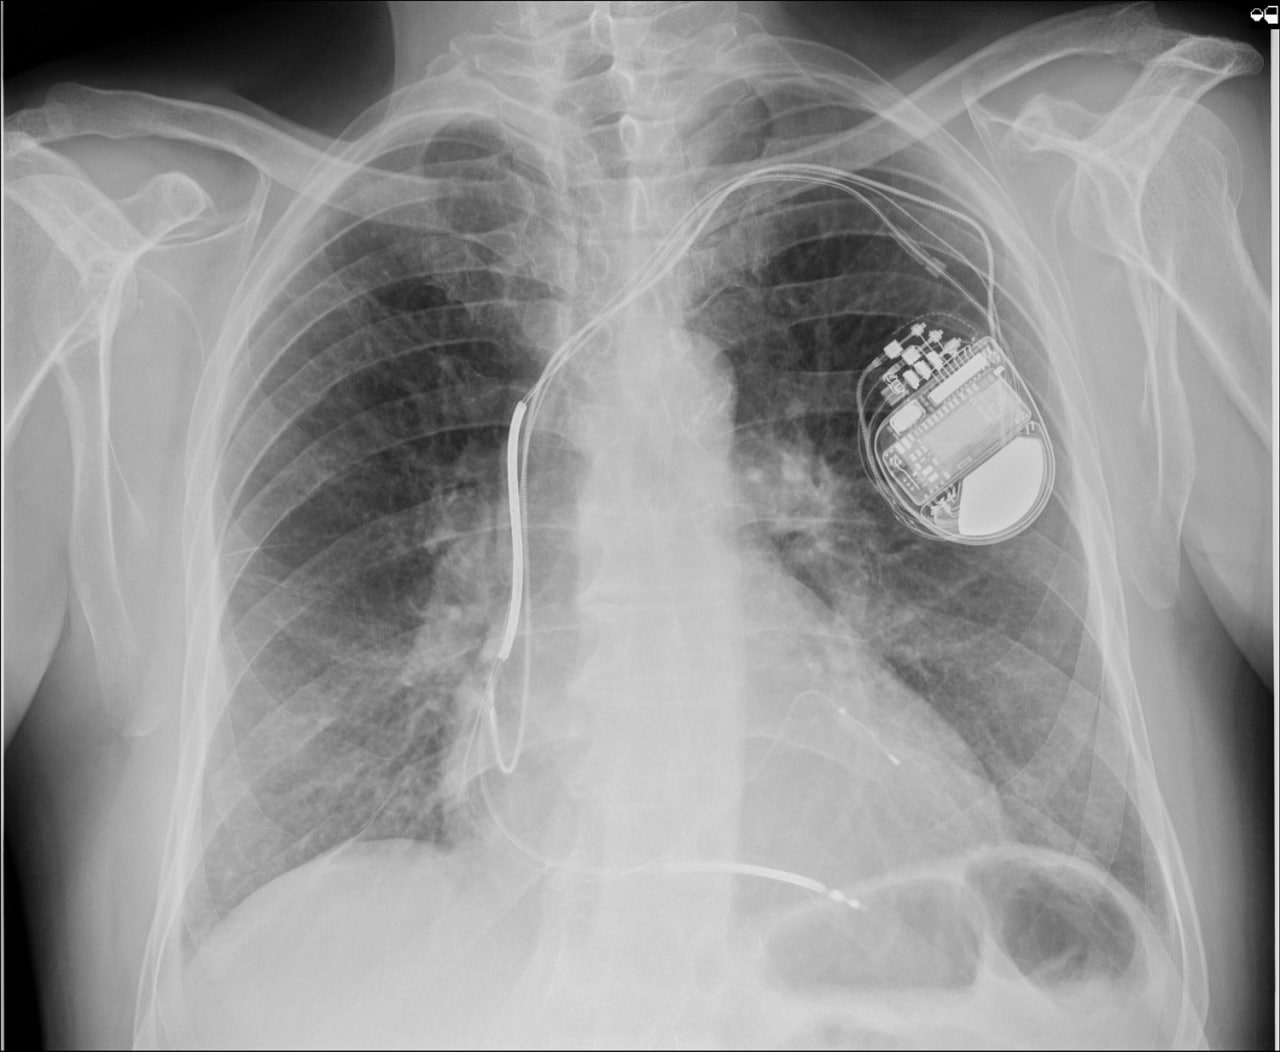

Очередному пациенту в ОККД имплантирован кардиовертер-дефибриллятор

На минувшей неделе в кардиохирургическом отделении №3 пациенту со сложной аритмией был имплантирован трёхкамерный кардиовертер-дефибриллятор. Вмешательство стало четвертым по счету, проведенным в стенах Областного кардиодиспансера менее чем за год. Впервые имплантация данного водителя ритма была проведена в ОККД 20 декабря 2023 года. Вмешательство выполнил заведующий КХО №3, к.м.н. Денис Сергеевич Терехов с командой врачей отделения.

«Имплантация кардиовертера-дефибриллятора с функцией ресинхронизирующей терапии требует тщательного подбора пациента, нуждающегося в данном устройстве, а также оценки потенциальной эффективности работы аппарата в каждом конкретном случае, при этом распространенность сердечной недостаточности в популяции не так уж мала. Ежегодно в Саратовской области выявляется от 30 до 50 человек, нуждающихся в операционной коррекции тяжелой сердечной недостаточности и желудочковых нарушений ритма с помощью многокамерных кардиовертеров-дефибрилляторов. До 2023 года в Саратовской области не было имплантировано ни одного такого устройства, но на сегодня мы успешно прооперировали уже четвертого пациента. Конечно, опыт пока небольшой, но на некоторых технических моментах внимание акцентировано. Надеемся на положительную перспективу развития этого направления аритмологии в нашем регионе и готовы набираться опыта, чтобы в дальнейшем максимально эффективно помогать бОльшему количеству пациентов», - отметил Денис Сергеевич.